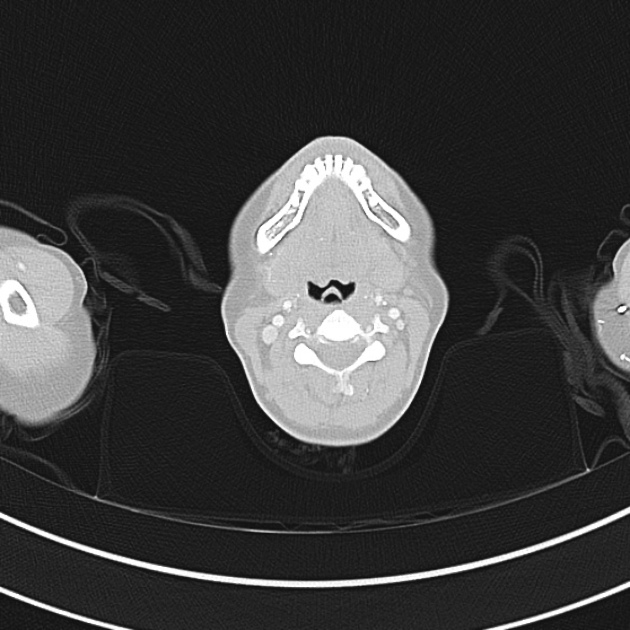

El diagnóstico de atelectasia pulmonar generalmente se realiza a través de una combinación de exámenes médicos y pruebas de diagnóstico. El médico puede ordenar una radiografía de tórax para identificar áreas de colapso pulmonar. Además, se pueden realizar pruebas como la tomografía computarizada, la oximetría y la broncoscopia para evaluar la gravedad de la afección y descartar otras condiciones pulmonares.